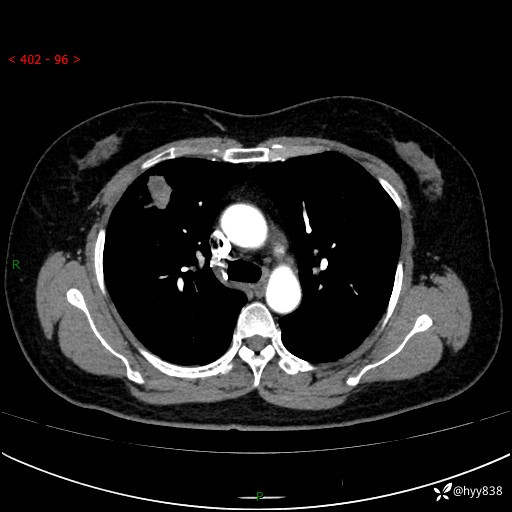

现病史:患者于2天余前无明显出现间断胸痛,无头痛、头晕,无心慌、胸闷、胸痛、呼吸困难、低热、盗汗,无腹痛、腹胀等不适,未进行进一步诊治。于2024.04.14在当地市人民医院行胸部CT检查提示:右肺上叶胸膜下结节。现患者为求进一步诊治,来我院就诊。以“肺肿物”收入我科。 患者自起病以来,精神可,睡眠可,饮食可,大小便正常,体重无明显改变。

胸部CT增强(肺窗,外院平扫)